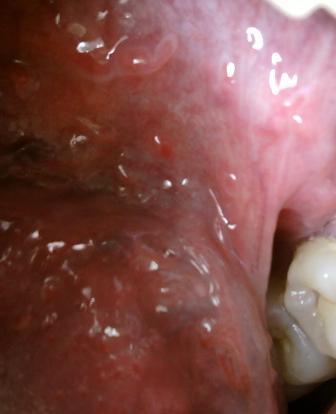

石家庄九州皮肤病医院 > 尖锐湿疣 > > > 哪些因素会导致尖锐湿疣性病复发尖锐湿疣病原体是人类乳头瘤病毒,专家温馨提示:患病之后应该及时就诊,不要因为任何原因耽误治疗,尖锐湿疣性病容易复发,这是让广大患者朋友们很头痛的问题,专家表示:以下几种原因会导致尖锐湿疣复发?希望广大患者朋友们应该注意:

哪些因素会导致尖锐湿疣性病复发不良的心态,很多人对于尖锐湿疣性病没有正确的认识和了解,患病之后羞于就医,专家表示:大家应该用科学的态度对待疾病,很多人由于害怕,恐惧等不良情绪导致疾病没有及时治疗,尖锐湿疣病毒有很多类型,但是不管是感染哪种类型而导致的疾病,都应该在初期进行科学的治疗。免疫力低下,熬夜,不良的饮食习惯以及不注重个人卫生等等都会导致加重,导致疾病复发。